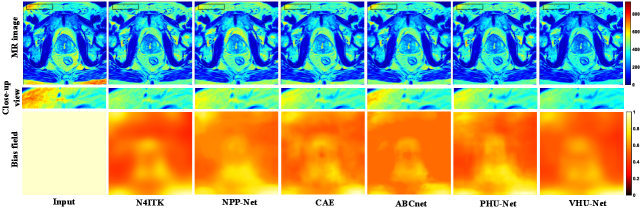

Refer to caption

Figure 8: The qualitative comparison on synthesized PanSegData. From top to bottom, the rows show the corrected MRI images, the zoomed-in local views, and the estimated bias fields.

4.5.2 Qualitative Comparison

Fig. 8 provides a qualitative comparison of bias field correction methods applied to MRI data with synthetic bias fields. The figure is structured in three rows: the corrected MRI images (top), zoomed-in views for local evaluation (middle), and the estimated bias fields (bottom). All MRI images are displayed using pseudo-color mapping to facilitate visual comparison across different methods. Additionally, bias fields are normalized to a consistent intensity scale, enabling clearer assessment of intensity variation and smoothness. In the top row, the corrected MRI images show that VHU-Net achieves superior bias removal, restoring tissue intensities to a visually uniform appearance while preserving anatomical detail. In contrast, CAE and PHU-Net leave noticeable residual inhomogeneities, especially in the right half of the regions. N4ITK introduces artificial intensity transitions near tissue boundaries. NPP-Net shows improvements over traditional methods but still fails to achieve local consistency comparable to VHU-Net. The second row provides a zoomed-in view of a selected region, enabling finer inspection of local intensity uniformity. VHU-Net exhibits the most consistent intensity distribution within small anatomical structures. Competing methods exhibit varying degrees of local inconsistency, which can negatively impact downstream tasks such as segmentation or quantitative analysis. The bottom row displays the estimated bias fields. Since the ground-truth bias is available in this simulation, qualitative comparison reveals that VHU-Net produces the most accurate and spatially smooth estimation, closely matching the ground-truth (GT) bias pattern. In comparison, CAE, ABCnet, PHU-Net, NPP-Net, and N4ITK fail to capture spatial variations. Enlarged and higher-resolution images are provided in the supplementary materials.